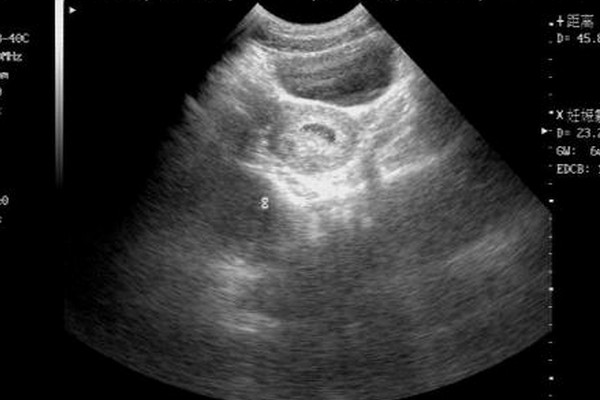

經常在圈子裡看到姐妹們在諮詢腹腔鏡的問題,當時看得我覺得這個手術是個很恐怖的事情,但當我親身去體驗了這個手術後其實覺得也沒有什麼,那麼今天就以自身的經歷分享一下這個好像很“可怕”的手術。瞭解敵人,才能戰勝敵人。希望姐妹們都能順順利利擁有自己的小孩。免受各種手術的苦。腹腔鏡知識早知道因為正常備孕一年不懷,查了各種基礎檢查沒問題。醫院B超監測排卵幾個週期後還是無果。這個時候,醫生就提出做宮腹腔鏡手術,...